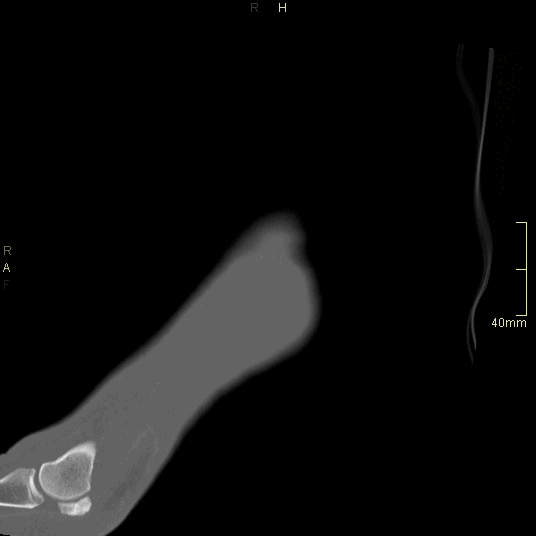

CT Ankle Non Contrast- Bone window (axial)

CT Ankle Non Contrast- Bone window (coronal)

CT Ankle Non Contrast- Bone window (sagittal)

CT Ankle Non Contrast- Soft tissue window (axial)